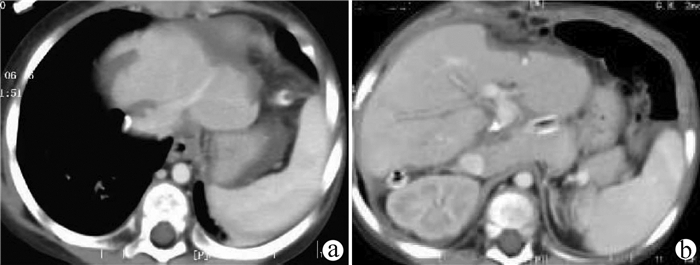

Primary hepatic carcinosarcoma with hepatocellular carcinoma: A case report

Ri LI, Huaibin GUO, Ze LIANG, Na LI, Junye WEN, Wanxing ZHANG

2021, 37(9): 2180-2182. DOI: 10.3969/j.issn.1001-5256.2021.09.034

Abstract(1261) HTML (266) PDF (4255KB)(62)

Abstract: